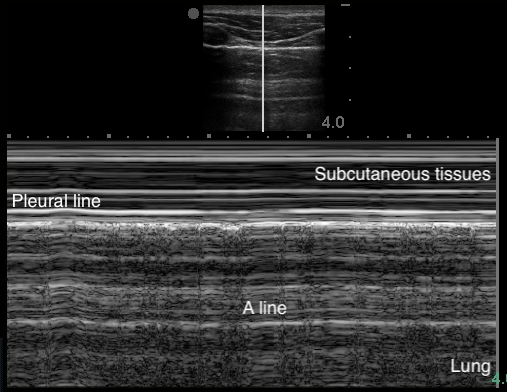

A-Lines

- Indicate normal aerated lung

- Horizontal reverberation artifact lines originating from the visceral pleura

- Figure 4. A-lines

Video 1. A-lines - Occur from the emitted US wave reflecting back and forth between the transducer and the pleural line

- The distance from transducer to pleural line is the same as between the equidistant intervals separating each subsequent A-line.

- The artifacts’ brightness decreases with depth as energy is lost through repeated reflections.